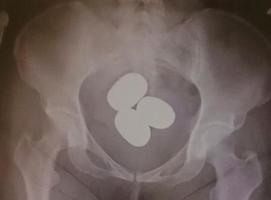

東京税関成田税関支署は24日、粉状の金を避妊具などに入れて体内に隠し、香港から成田空港へ密輸するケースが急増していると明らかにした。今年1〜3月に押収しただけで時価総額は約12億円に上る。不安定な国際情勢を背景に金の価格は高騰しており、正規の輸入で納めなければならない消費税を免れ、利ざやを得る目的とみている。

成田税関支署によると、成田空港で粉状の金の摘発は昨年1年間で23件、計約31キロ。今年は3月までに30件、計約45キロで、いずれも香港や中国籍の旅客が、粉状の金を空港到着後などに体内に隠し、持ち込もうとした。中高年の女性が多く、複数の塊に分けて約2・7キロ分を密輸しようとした男性もいたという。